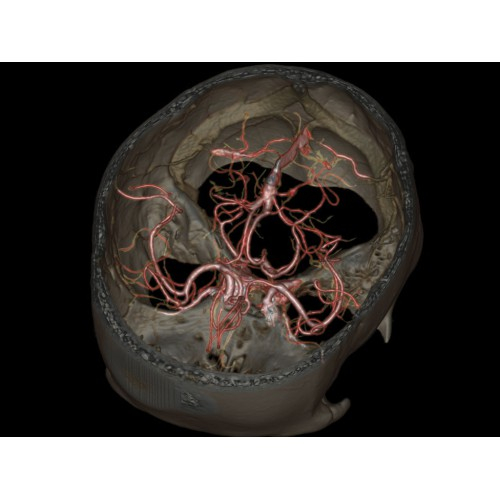

Компьютерный томограф GE Brivo CT385 представляет собой современное диагностическое оборудование, сочетающее высокую точность исследований с повышенным комфортом для пациентов. Этот аппарат открывает новые возможности для детальной визуализации анатомических структур.

Позволяет проводить комплексные исследования всех анатомических зон, включая нейровизуализацию, ангиографию, исследования органов грудной и брюшной полости. Особенно эффективен для раннего выявления онкологических заболеваний.